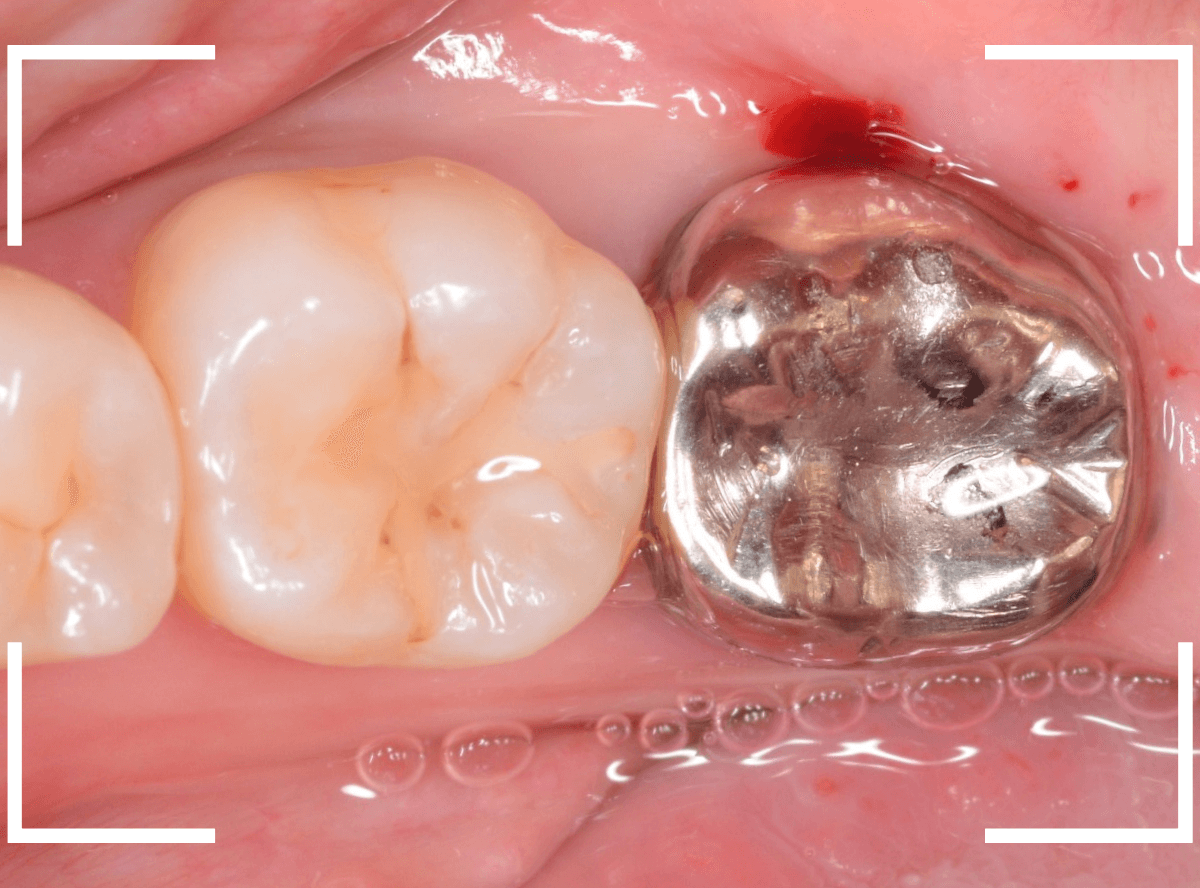

「古くなった銀歯を白くしたい」というご希望の患者さんです。

たしかに、冠が少し傷ついたり、すり減ったりしてる感じもありますね。

審美性も清掃性も高い、ジルコニア・クラウンで作り直す事になりました。

銀歯(メタル・クラウン)を外すと、大きめの歯の土台、メタル・コアが入っていました。

このままジルコニア・クラウンで作り直す事もできますが、一旦メタル・コアを除去して、土台から作り直す事にします。

歯を傷つけないように、時間をかけて慎重にコアを削り取ります。